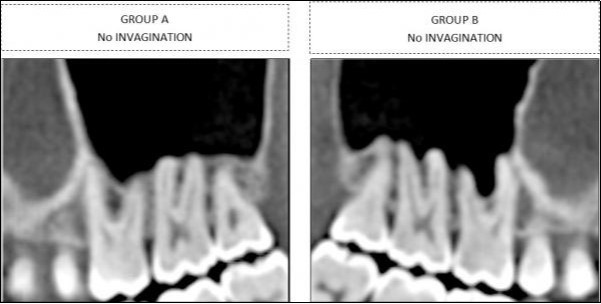

Findings for the molars were classified into two groups, depending upon whether sinus-floor invagination was present between the roots (Group B) or not (Group A) (Figure 2).

Figure 2.Classification in two different categories for molars , based on sinus invagination

Classification in two different categories for molars , based on sinus invagination